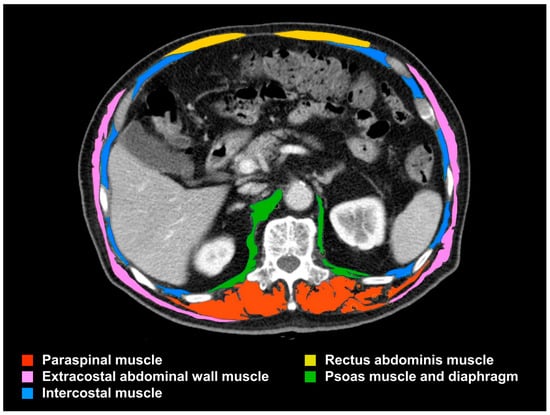

The SMA at the L1 level was measured as described previously [20]. In brief, CT Hounsfield unit ranges of −29 to 150 were considered skeletal muscle, and ranges of −190 to −30 were considered adipose tissue. The skeletal muscle measurements from the transverse cross-sectional CT image consisted of five major components, as shown in Figure 2: (1) the paraspinal muscle, (2) the extracostal abdominal wall muscle, (3) the intercostal muscle, (4) the rectus abdominis muscle, and (5) the psoas muscle and diaphragm. Two blinded observers independently measured the cross-sectional areas (cm2) of the five skeletal muscle components using a freehand module provided by the PACS workstation (G3 Infinitt PACS; Infinitt Healthcare, Seoul, Republic of Korea). The SMIs (cm2/m2) were determined by standardizing the measured cross-sectional SMA for height. L1 SMA and SMI measurements demonstrated excellent reproducibility and interobserver agreement in a previous study [20]. Subsequently, we stratified the entire study population into four groups based on sex-specific quartiles of L1 SMI to explore the potential existence of a dose-dependent relationship between skeletal muscle mass and adverse clinical outcomes. The sex-specific quartiles for L1 SMI were 30.00, 34.50, and 39.00 cm2/m2 for men and 24.50, 29.00, and 32.30 cm2/m2 for women. In the available cases, the skeletal muscles at the L3 level were measured as a composite of the abdominal wall, paraspinal, and psoas muscles (Figure S1) [17] to assess the correlation with the L1 skeletal muscle measurements.

Figure 2.

CT-based assessment of L1 skeletal muscle mass. The axial skeletal muscle area at the L1 level comprises five major components: paraspinal muscle, extracostal abdominal wall muscle, intercostal muscle, rectus abdominis muscle, and psoas muscle and diaphragm. CT, computed tomography; L1, first lumbar vertebra.